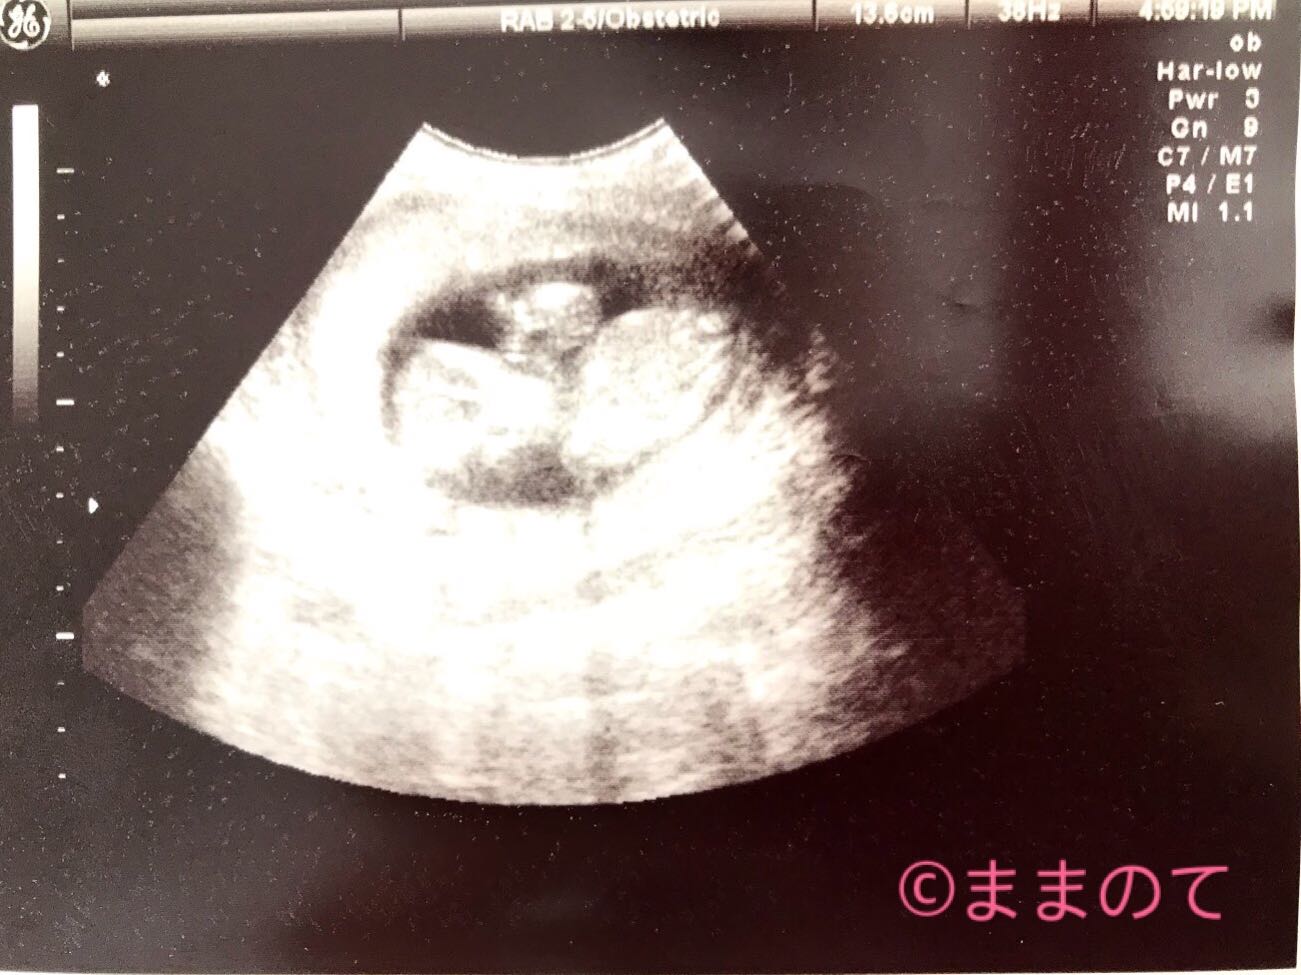

妊娠14週の赤ちゃんのエコー画像

妊娠14週0日の胎児のエコー画像です。体重58g、身長13.6cm、BPD2.8cmに成長しています。顔を正面に向け、左手は顔の横で手を振っているようなポーズをとり、指先にはうっすらと5本の指がみえていますよ。股間のところに丸く写っているのは小さな足です。性別はまだわかりません。